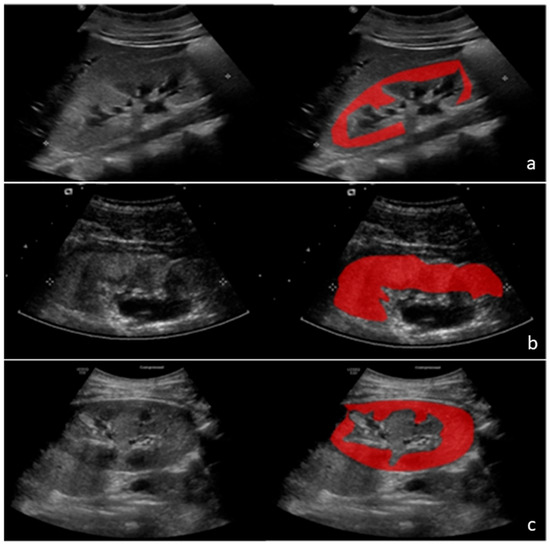

2.2.1. Region of Interest Selection